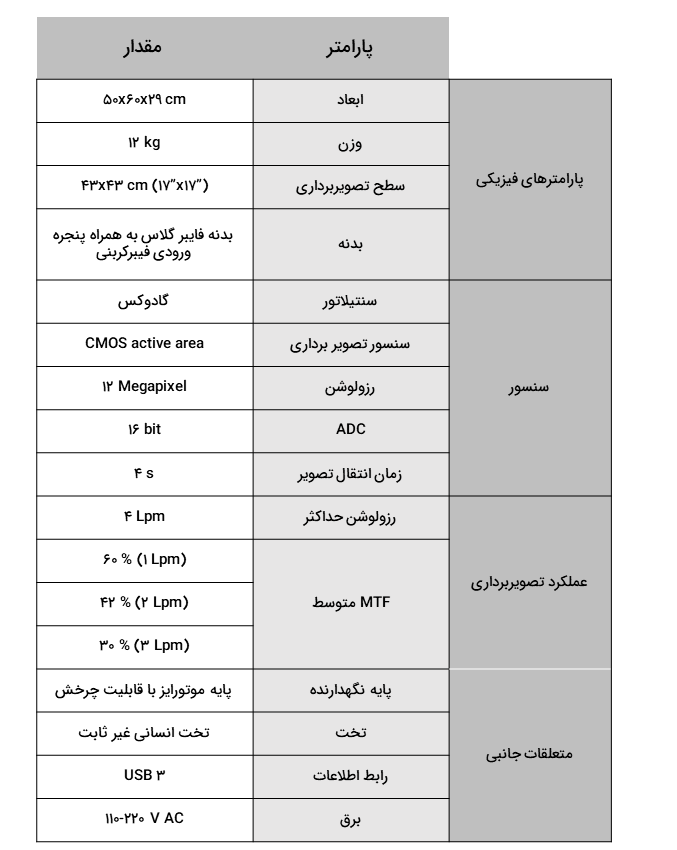

دتکتور رادیولوژی

1717 RX

آشکار ساز RX 1717 یک دتکتور X-Ray مناسب رادیولوژی دیجیتال (DR) است که عملکردی مشابه با فلت پنل های امروزی دارد. این آشکار ساز برای اولین بار در کشور توسعه داده شده است و تکنولوژی متمایزی نسبت به فلت پنل دارد. دتکتور RX 1717 هم می تواند به صورت تک دتکتور و هم به صورت دو دتکتور استفاده شود. در حالت تک دتکتور دستگاه به همراه یک استند با قابلیت دوران و در حالت دو دتکتور نیز دستگاه به همراه یک تخت و یک استند جداگانه ارائه می شود. تکنولوژی متمایز RX 1717 باعث می شود تا از لحاظ ابعاد با فلت پنل ها کمی تفاوت داشته باشد. با این حال،کیفیت تصویر RX 1717 از بسیاری از فلت پنل های موجود در بازار بهتر بوده و در عین حال قیمت مناسب تری از آن ها دارد. قابلیت اطمینان و تعمیرپذیری این دتکتور به سبب تفاوت تکنولوژی متفاوت آن، بسیار بهتر از فلت پنل بوده و از طرفی در صورت بروز هرگونه ایراد، شرکت رایومد توانایی رفع کامل آن را داشته و نسبت به این موضوع اقدام خواهد کرد.